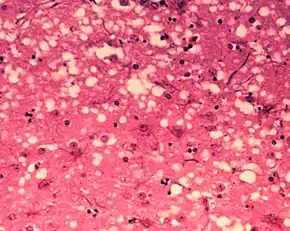

BSE prions are misfolded forms of the particular brain protein called prion protein. When this protein is misfolded, the normal alpha-helical structure is converted into a beta sheet. The prion induces normally-folded proteins to take on the misfolded phenotype in an exponential cascade. These sheets form small chains which aggregate and cause cell death. Massive cell death forms lesions in the brain which lead to degeneration of physical and mental abilities and ultimately death.[15] The prion is not destroyed even if the beef or material containing it is cooked or heat-treated under normal conditions and pressures.[16] Transmission can occur when healthy animals come in contact with tainted tissues from others with the disease, generally when their food source contains tainted meat.[2]

Diagnosis of BSE continues to be a practical problem. It has an incubation period of months to years, during which no signs are noticed, though the pathway of converting the normal brain prion protein (PrP) into the toxic, disease-related PrPSc form has started. At present, no way is known to detect PrPSc reliably except by examining post mortem brain tissue using neuropathological and immunohistochemical methods. Accumulation of the abnormally folded PrPSc form of PrP is a characteristic of the disease, but it is present at very low levels in easily accessible body fluids such as blood or urine. Researchers have tried to develop methods to measure PrPSc, but no methods for use in materials such as blood have been accepted fully.

The traditional method of diagnosis relies on histopathological examination of the medulla oblongata of the brain, and other tissues, post mortem. Immunohistochemistry can be used to demonstrate prion protein accumulation.[25]